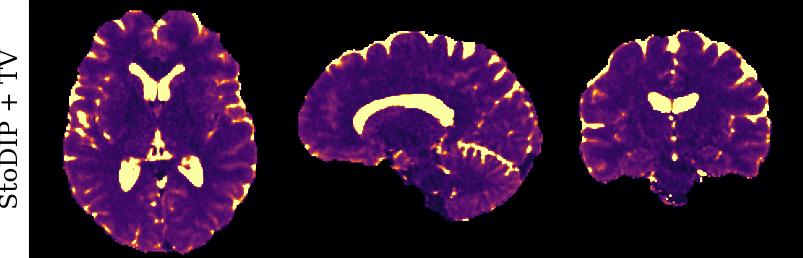

To monitor performance progress, we mapped TSMI to Q-Maps every five epochs. To mitigate the lengthy processing times associated with Dictionary Matching, we implemented a fully connected network to directly map TSMI to Q-Maps [5], significantly reducing processing time. However, for the final assessment, we employed DM on all techniques at the conclusion of the training process (epoch 500). We report in Table 1 the Mean Average Percentage Error (MAPE) of T1/T2 maps, and Peak Signal-to-Noise Ratio (PSNR) and Structural Similarity (SSIM) Index for T1/T2 and normalised PD. To accompany these metrics we also offer in Fig. 2 the reconstructed T1 and T2 maps for the different approaches.

The training and validation loss (Fig. 1) served as valuable guides for architecture and training design. To demonstrate this, we selected a subset of experiments in which we kept certain variables fixed and only modified the one under inspection. From Fig. 1 (a)-(d), MAPEs curves show there is a clear setting with the preferred performance. Specifically, from Fig. 1a, it is evident that using DRUNet yields a clear improvement over the original architecture. This could be attributed to the utilisation of residual units in addition to other architecture differences, such as the choice of upsampling operator (transpose convolution for DRUNet and trilinear for DIP). The choice of input (Fig. 1b) demonstrated a consistent pattern among the tested options, with low rank (conjugate gradient) initialiser marginally outperforming the others. Fig. 1cshows that by epoch 100, stochastic approaches exhibit lower reconstruction errors compared to non-stochastic methods. For example, adaptive LR with stochastic training yields a combined MAPE of 61.40% (17.09% T1 and 44.31% T2) vs. 213.69% (35.50% T1 and 178.19% T2) for the non-stochastic method. This fast convergence is due to adaptive LR and stochastic updates across coils. Despite similar execution times ( 34 min for stochastic with adaptive LR vs. 32 min for non-stochastic with fixed LR), the rapid error reduction makes StoDIP more attractive for training.. To assess the early stopping of DIP models, a key element, we present Fig. 1d. The original work by Ulyanov et al. [21] used 2k iterations, while Hamilton et al. [12] used 30k. In contrast, our settings show StoDIP achieving competitive performance in under 500 epochs (4k iterations) on the entire volume. However, StoDIP can overfit to k-space measurements, affecting reconstruction accuracy, and thus the iteration at which it stops could have a greater impact. We show that adding a spatial penalty term addresses overfitting and instabilities. This is supported by the maps in Fig.2, supplementary material Figures 1-3, and metrics in Table 1. StoDIP reconstructions lack aliasing artifacts, and the TV regularizer (StoDIP + TV) further improves Q-Map reconstruction by reducing checkerboard artifacts observed in StoDIP outputs alone.